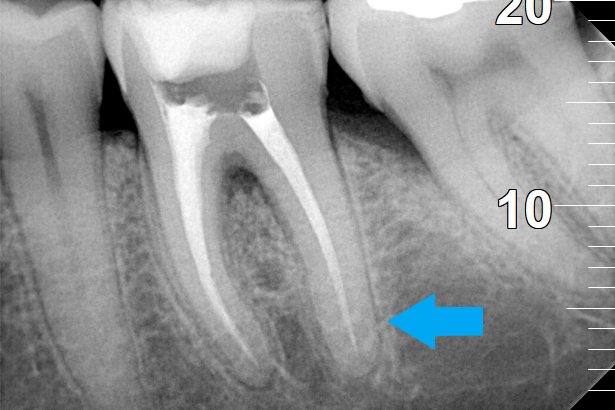

Root canal treatment

BEFORE

AFTER